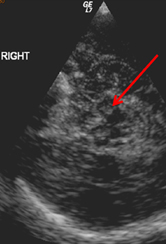

Zahlreiche Studien, unter anderem auch aus Innsbruck, belegen, dass viele Parkinson-Patient:innen schon vor dem Auftreten der ersten motorischen Symptome andere Dysfunktionen entwickeln. Im Frühstadium werden etwa die chronische Obstipation (Verstopfung), aber auch Stimmungsstörungen mit Depressivität oder Panikattacken beobachtet. Aber auch die Störung des Geruchssinns und die nächtliche REM-Schlafstörung können frühe Indikatoren für das Parkinson-Syndrom sein. „Mindestens 50 Prozent der Patient:innen zeigen bis zehn Jahre vor Beginn der Krankheit derartige Symptome“, bestätigt Prof. Poewe ein Forschungsergebnis aus einer, in Zusammenarbeit mit Forscherkolleg:innen in Barcelona durchgeführten Untersuchung. Die „prämotorische“ Phase kann Monate bis Jahre in Anspruch nehmen und bildet somit ein wichtiges Zeitfenster für die Frühdiagnostik. Diagnostisches Potenzial liegt aber auch in der Bildgebung: So konnte in mehreren Studien die prädiktive Relevanz von Ultraschallmerkmalen im Mittelhirn bestätigt werden.